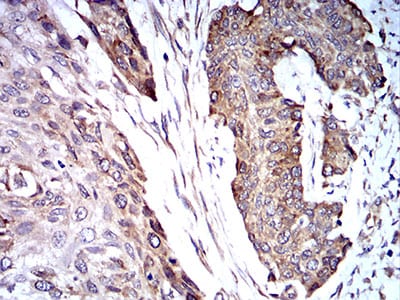

Immunohistochemical analysis of paraffin-embedded human cervical cancer tissues using TRIM25 mouse mAb with DAB staining.

Immunohistochemical analysis of paraffin-embedded human esophageal cancer tissues using TRIM25 mouse mAb with DAB staining.